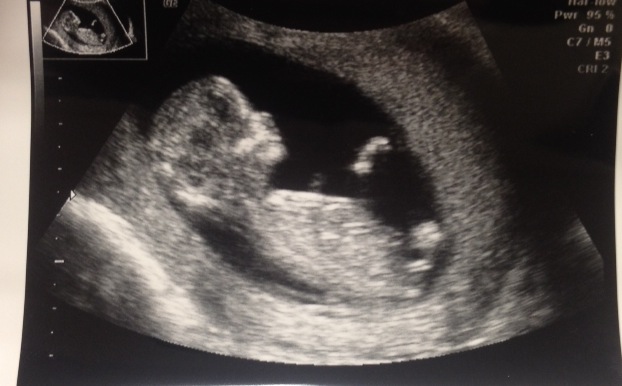

This was at 12 weeks and 5 days.Attachment 20779

I really think BOY

How can you tell?? I have heard about the nub theory and thought it looked like it was pointing up too, but just wanted to get some other opinions!

my guess is by the shape of the skull. Very boyish!